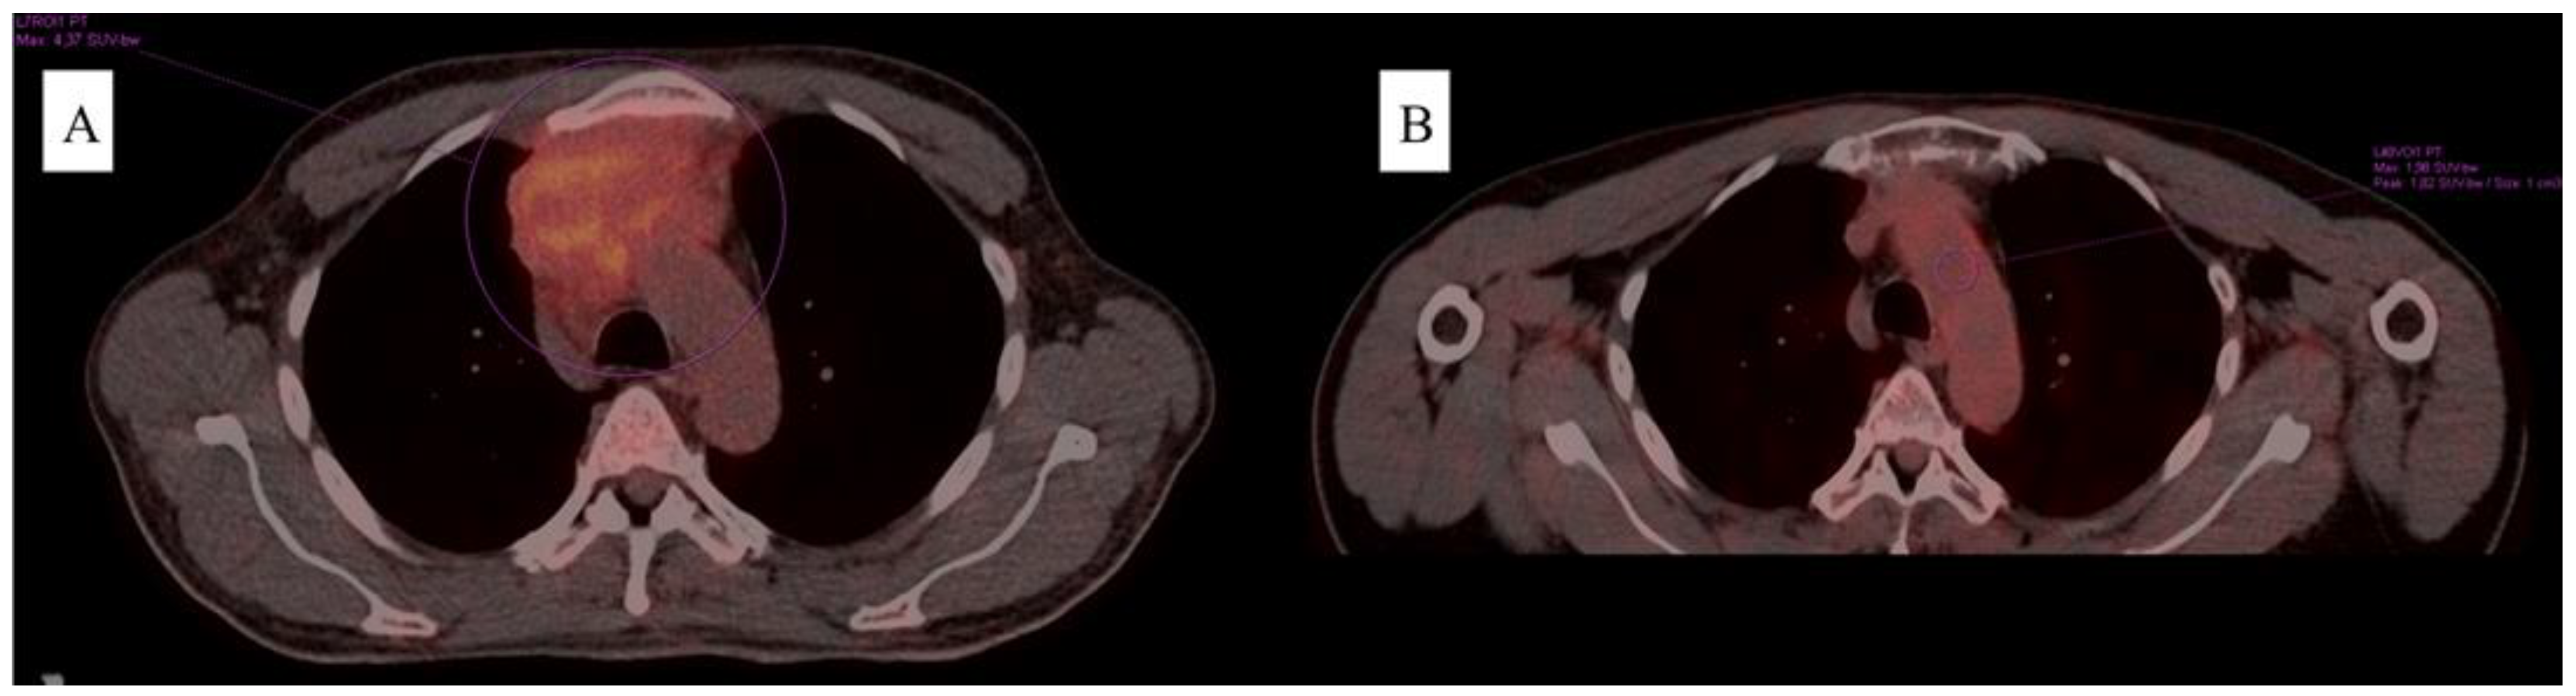

3. Case 1

4. Case 2